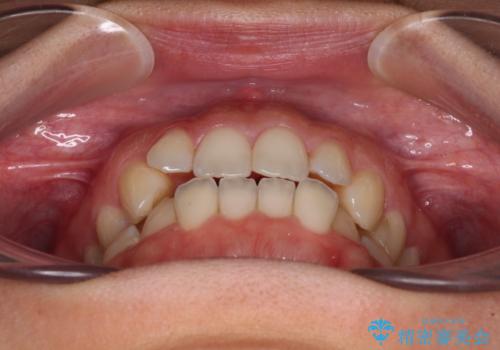

【モニター】オープンバイトをインビザライン矯正で治す

- 前歯の開咬を気にして来院された患者様です。

開咬の治療は、前歯を閉じるように動かすとともに、上下臼歯を圧下(骨内にめり込ませる)させることで進めて行きます。

インビザラインは臼歯の圧下を効果的に行えるため、インビザラインを用いて矯正治療を行うこととしました。